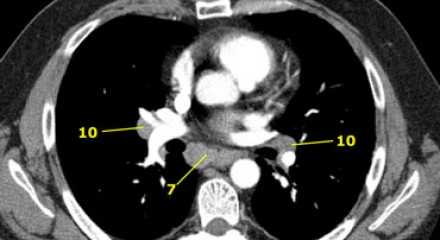

7. Подкаринальные лимфатические узлы

Эти лимфатические узлы расположены ниже уровня бифуркации трахеи (карины), но не относятся к нижнедолевым бронху и артерии. Справа они располагаются каудальнее нижней стенки промежуточного бронха. Слева они располагаются каудальнее верхней стенки нижнедолевого бронха. Слева лимфатический узел 7 группы справа от пищевода.

9. лимфатические узлы легочной связки

Данные лимфатические узлы лежат в пределах легочной связки, в том числе и по ходу нижней легочной вены. Легочная связка представлена дупликатурой медиастинальной плевры охватывающей корень легкого.

10. лимфатические узлы корня легкого

Лимфатические узлы корня расположены проксимальнее долевых узлов, но дистальнее медиастинальной дупликатуры и узлов промежуточного бронха справа.

Все лимфатические узлы 10-14 групп являются N1 узлами, так как они находятся вне средостения.